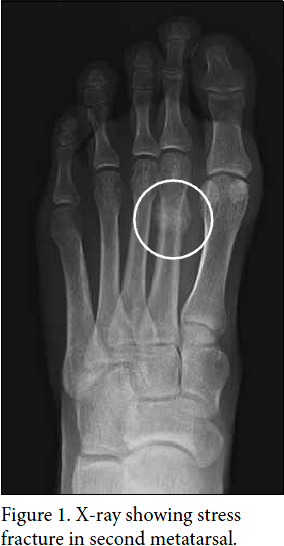

To confirm the presence of a stress fracture, your doctor may need to order an x-ray (see Figure 1). If the x-ray does not show a stress fracture, a bone scan (see Figure 2) or magnetic resonance imaging (MRI) may be needed.